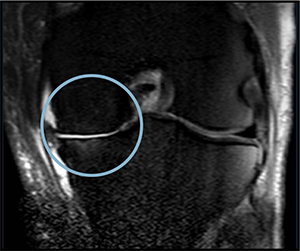

Before starting cell therapy, patients undergo a magnetic resonance imaging (MRI) or computed tomography (CT) scan to assess the condition of the bone and soft tissues of the knee.